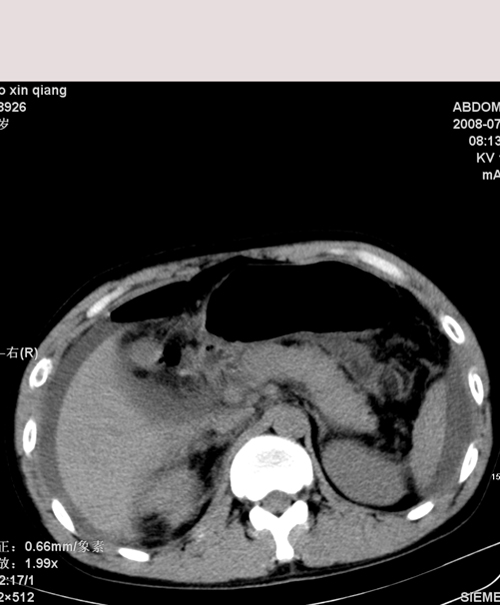

以下是引用随光逐影在2008-7-15 11:18:00的发言:[br]考虑为:1)腹部空腔脏器穿孔。2)右肾破裂并肾包膜下血肿,肾盂积血。3)腹水(血)。

以下是引用muzi888在2008-7-15 10:45:00的发言:[br]大量腹腔积液,气腹,肾皮质弧形高密度影,诊断;1 空腔脏器穿孔 2 右肾包膜下血肿

以下是引用yangyudong333在2008-7-15 12:06:00的发言:[br]考虑为:1)腹部空腔脏器穿孔。2)右肾破裂并肾包膜下血肿,肾盂积血。3)腹水(血)。